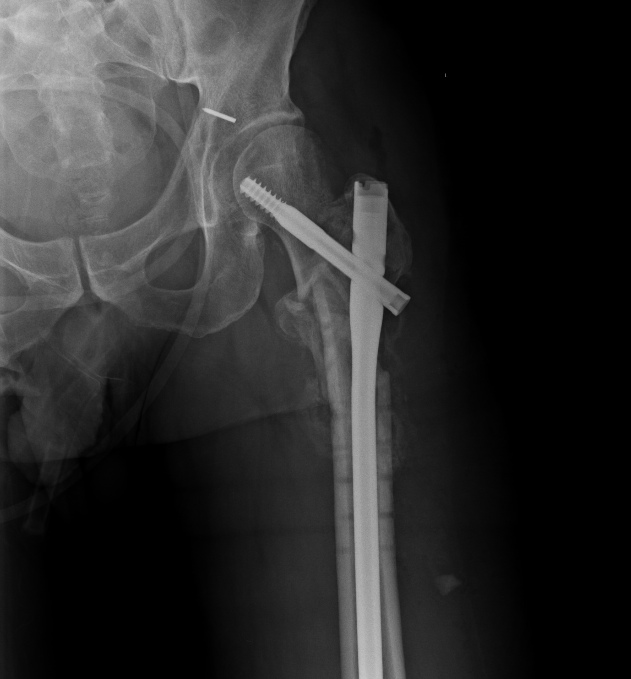

Спасибо за интересное обсуждение. Действительно, головка сохраняет сферичность, кровоснабжение ее должно быть сохранено, так что есть смысл сделать реконструкцию.

Удалили DHS, пришлось вытащить единым блоком, винт прокручивался. . Опознавательных знаков на имплантате не обнаружили. Дополнительный винт был введен во фрагмент, который оказался не связан ни с чем, так что удалили и его После удаления была хорошая подвижность. Сделали остеосинтез вот так. Комментарии и критика приветствуются.

Кстати, если посмотреть на боковую проекцию, так хорошо видно, что над винтом располагается отверстие от DHS, прорезавшее верхнюю стенку. Второй винт болтался бы там, мешая зарастанию и увеличивал бы риск прорезывания данной конструкции.